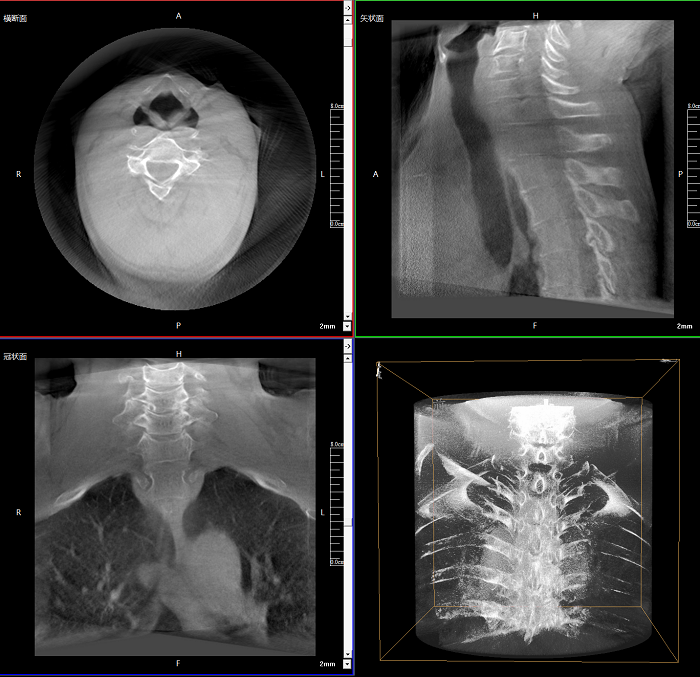

三維成像 全面觀察

任意視角、任意切面觀察

術(shù)中實(shí)時(shí)生成橫斷面、矢狀面、冠狀面及三維影像,可在任意切面、任意角度評估植入物和解剖結(jié)構(gòu)的相對位置。

Clinical picture

臨床圖片